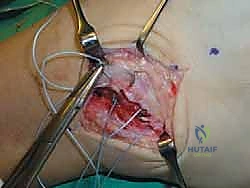

الخطوة الخامسة: زراعة خطاطيف الخياطة (Suture Anchors)

هنا تتجلى التقنيات الحديثة. بدلاً من حفر ثقوب كبيرة في العظم كما كان يحدث قديماً، يستخدم أ.د. محمد هطيف خطاطيف دقيقة جداً (Suture Anchors) مصنوعة من مواد متوافقة حيوياً (Bio-composite) أو التيتانيوم. يتم زرع خطاف أو خطافين في عظمة الشظية، وتكون هذه الخطاطيف محملة بخيوط جراحية فائقة القوة.